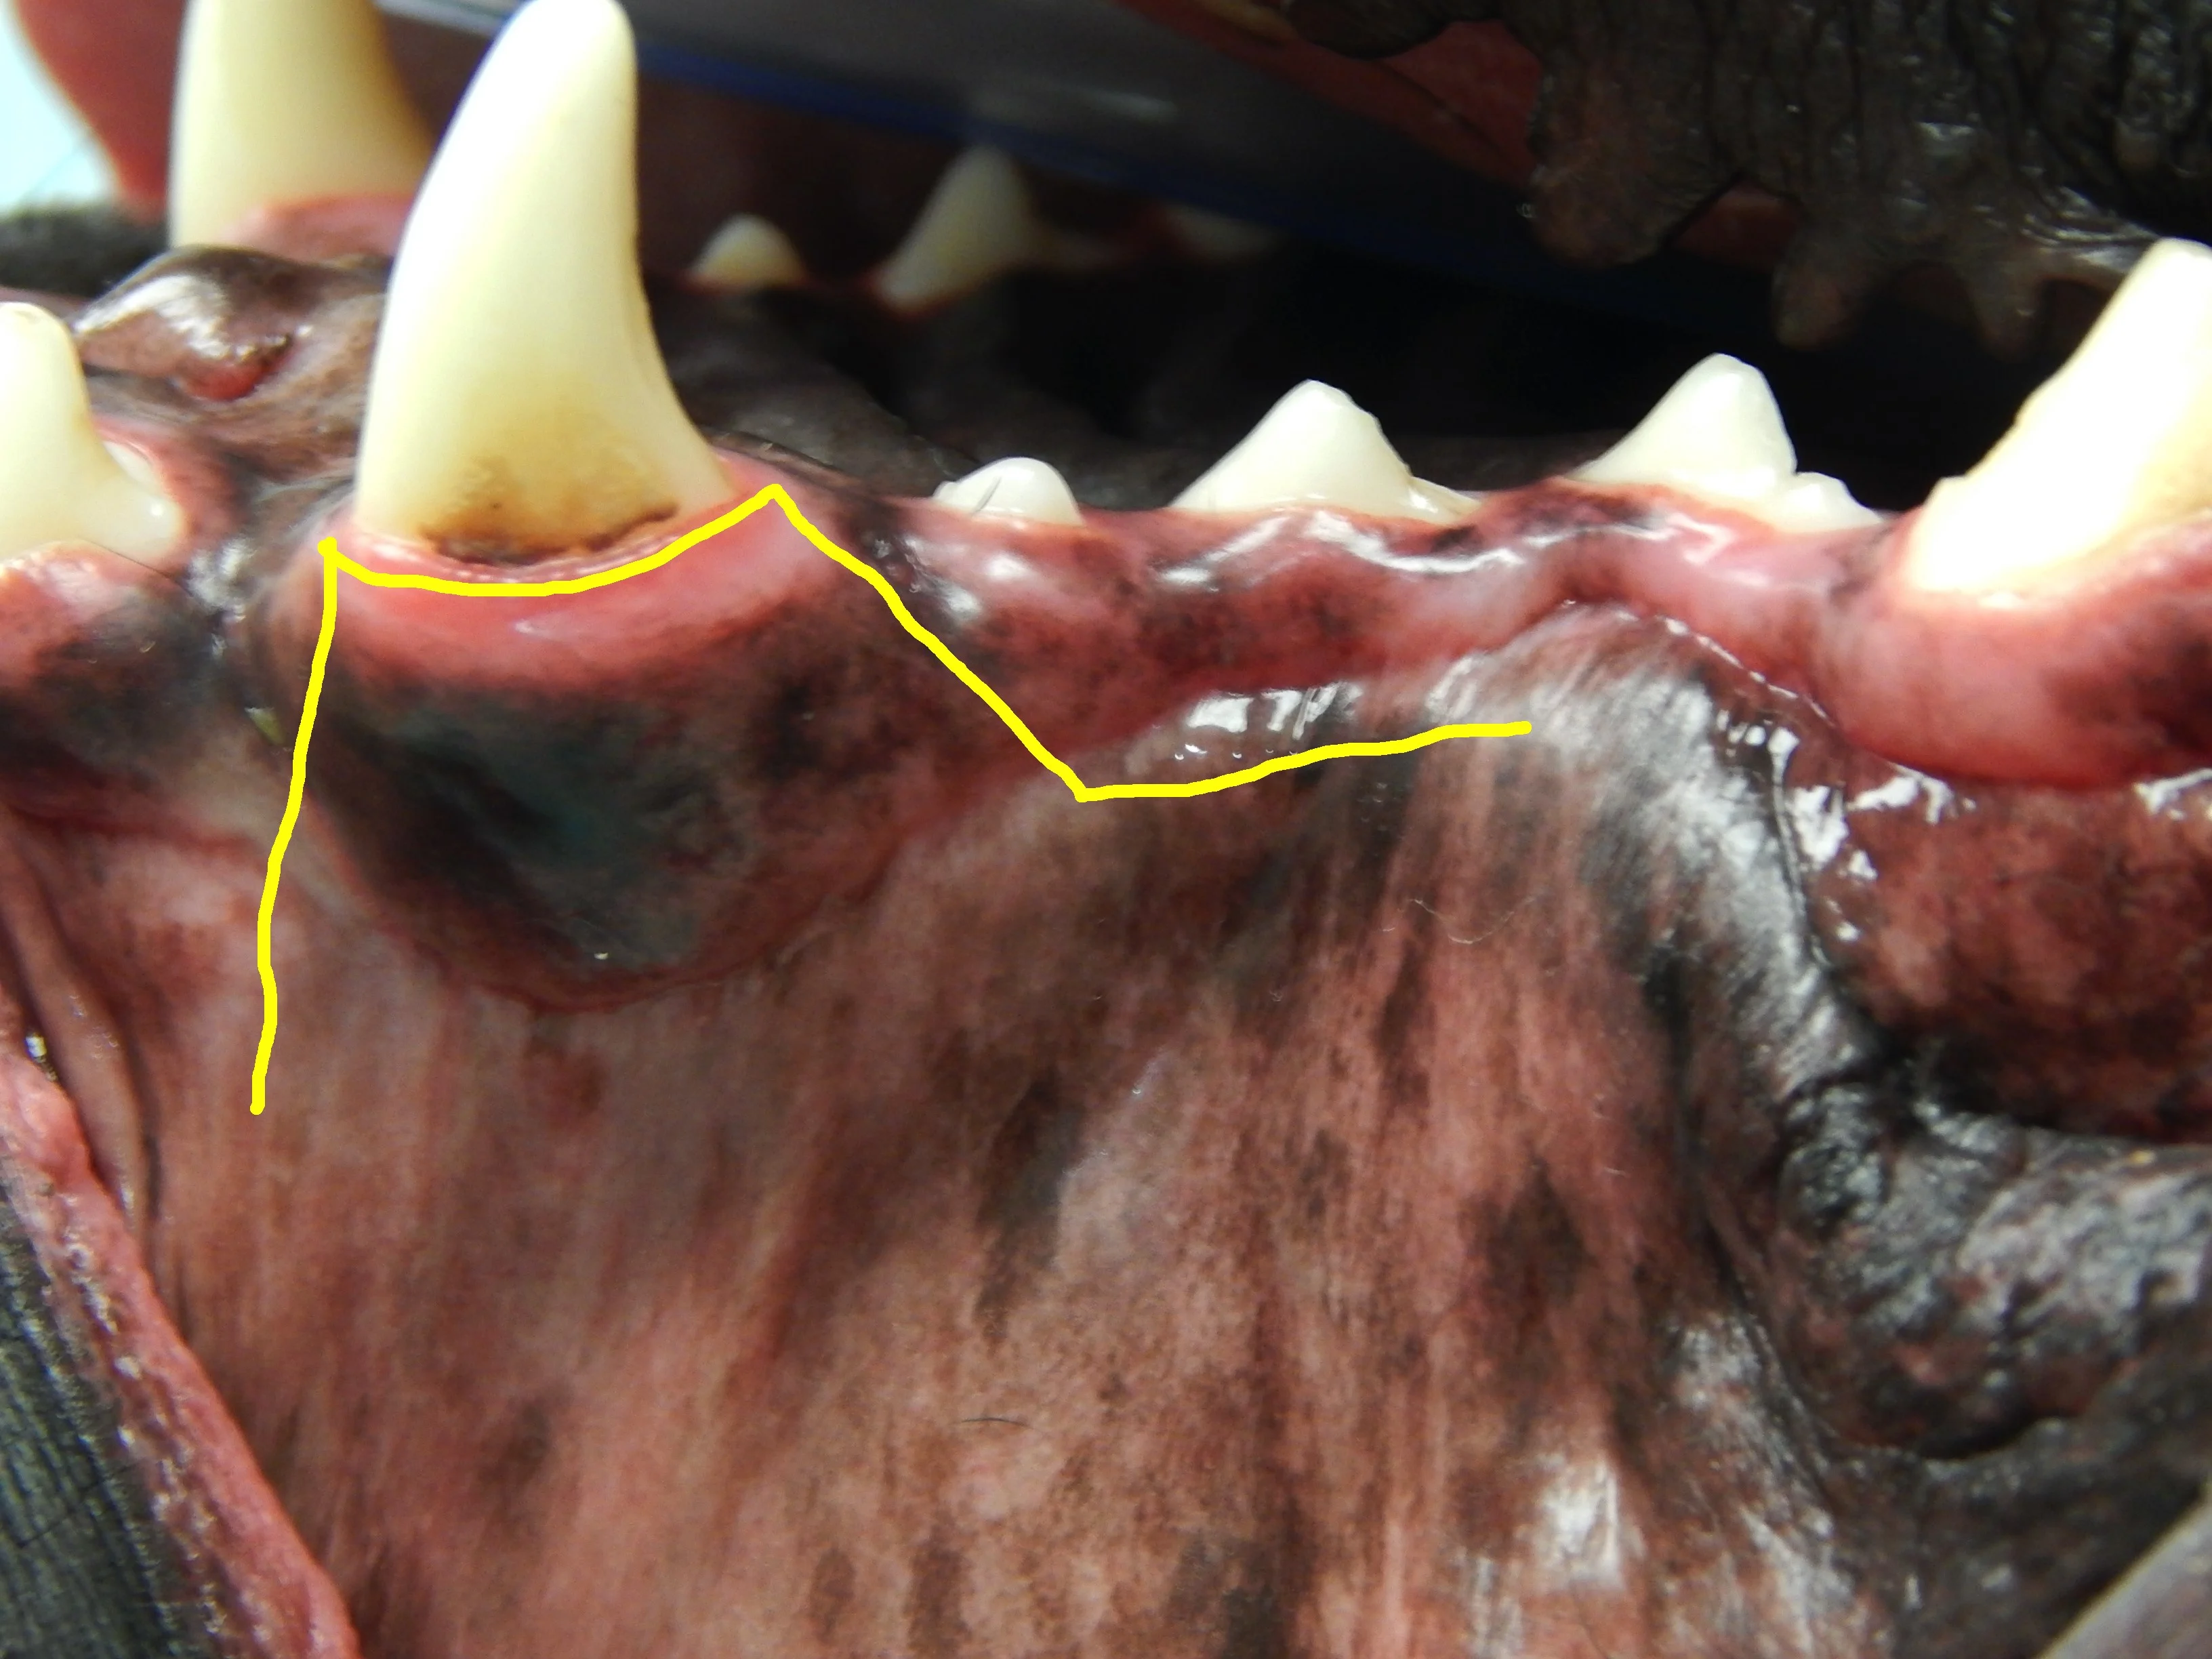

Closing a mucogingival flap under tension increases the risk for dehiscence,4 and understanding the options available for complete flap mobilization (eg, proper release of the periosteum, preplanning advancement flap design, releasing incision placement) is important when reducing tension on a flap. Damaged tissue should be removed prior to closure of the wound. Patients with severe periodontal disease can have significant loss of the buccal-attached gingiva and mucosa (Figure 3). Tissue that is lost, either due to pre-existing disease or surgical trauma, makes closure of a gingival flap more difficult.

Calculus accumulation and significant loss of the attached gingiva (arrows) of the left maxillary canine tooth. Gingival recession can make surgical closure more difficult and increase the potential for postoperative complications.